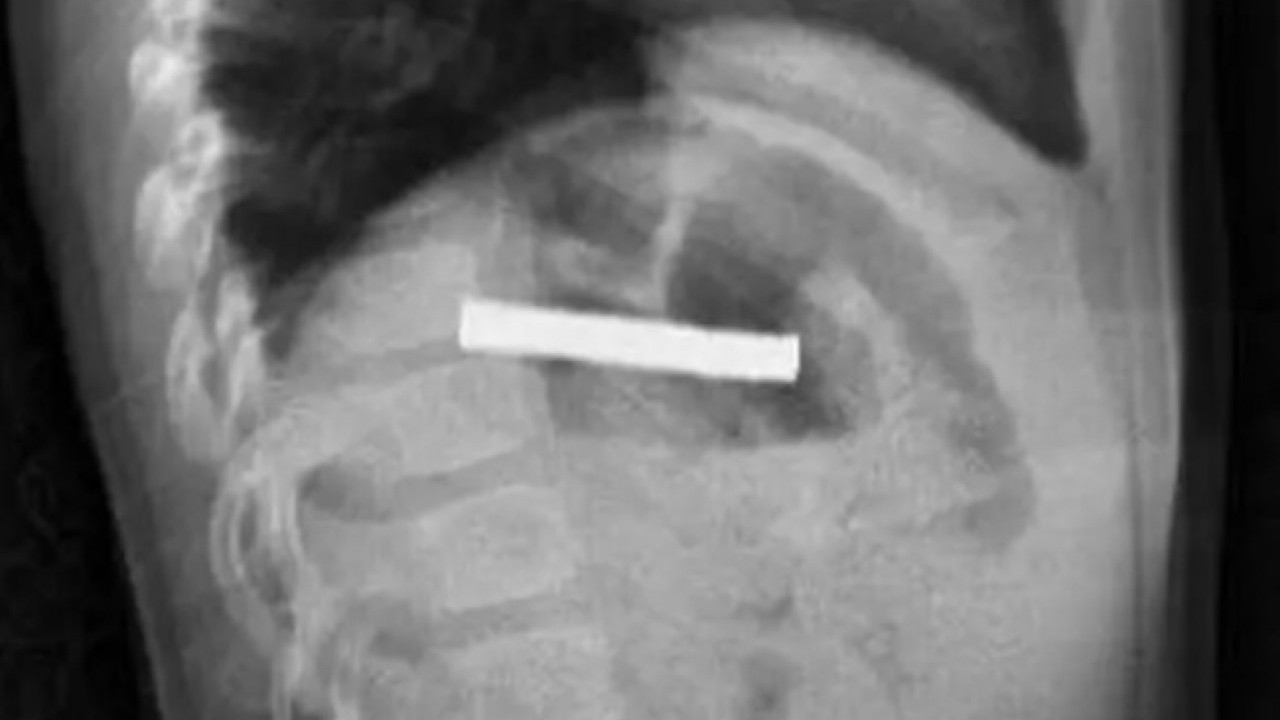

Elazığ'da mıknatıs yuttuğu için midesinde hasar meydana gelen 3 yaşındaki çocuğa endoskopi uygulandı. Alınan bilgiye göre, Erzurum'da bir çocuk evde bulunan 19 tane mıknatısı yuttu.

MIKNATISLARIN YEMEK BORUSUNA YAPIŞTIĞI TESPİT EDİLDİ Fırat Üniversitesi Çocuk Gastroenteroloji Hepatoloji ve Beslenme Bilim Dalı Başkanı Prof. Dr. Yaşar Doğan, çocuk hastanın yemek borusuna yapışmış 19 mıknatısı endoskopik yöntemle çıkardı.

Mıknatıslar uzun süre yemek borusunda takılı kaldığı için yemek borusu ve mide girişinde zedelenmeler olurken, çocuğun sağlık durumunun iyi olduğu ve taburcu edildiği öğrenildi./